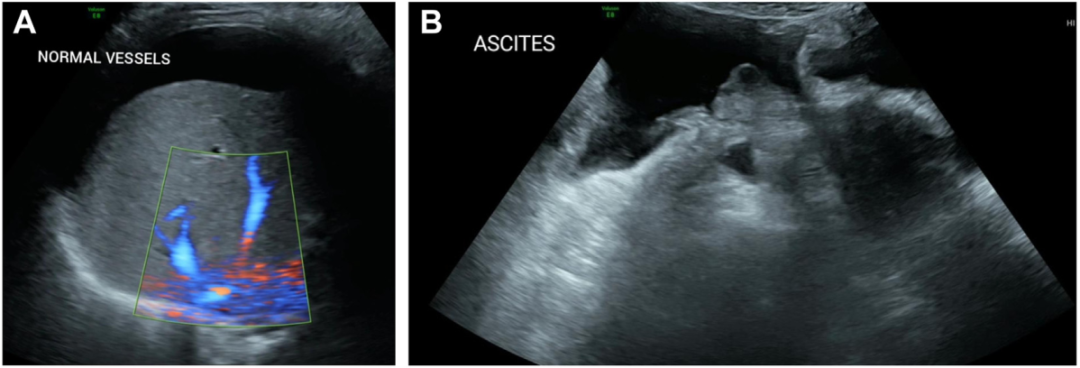

- Gut Microbes:补充内源性健康肠道代谢物可逆转IBD患者粪便内容物诱导的体外和离体上皮功能破坏 该模型系统评估了IBD肠道微环境对上皮屏障、炎症及能量代谢的特异性破坏,并从中筛选出能够逆转损伤、促进修复的关键代谢物。……